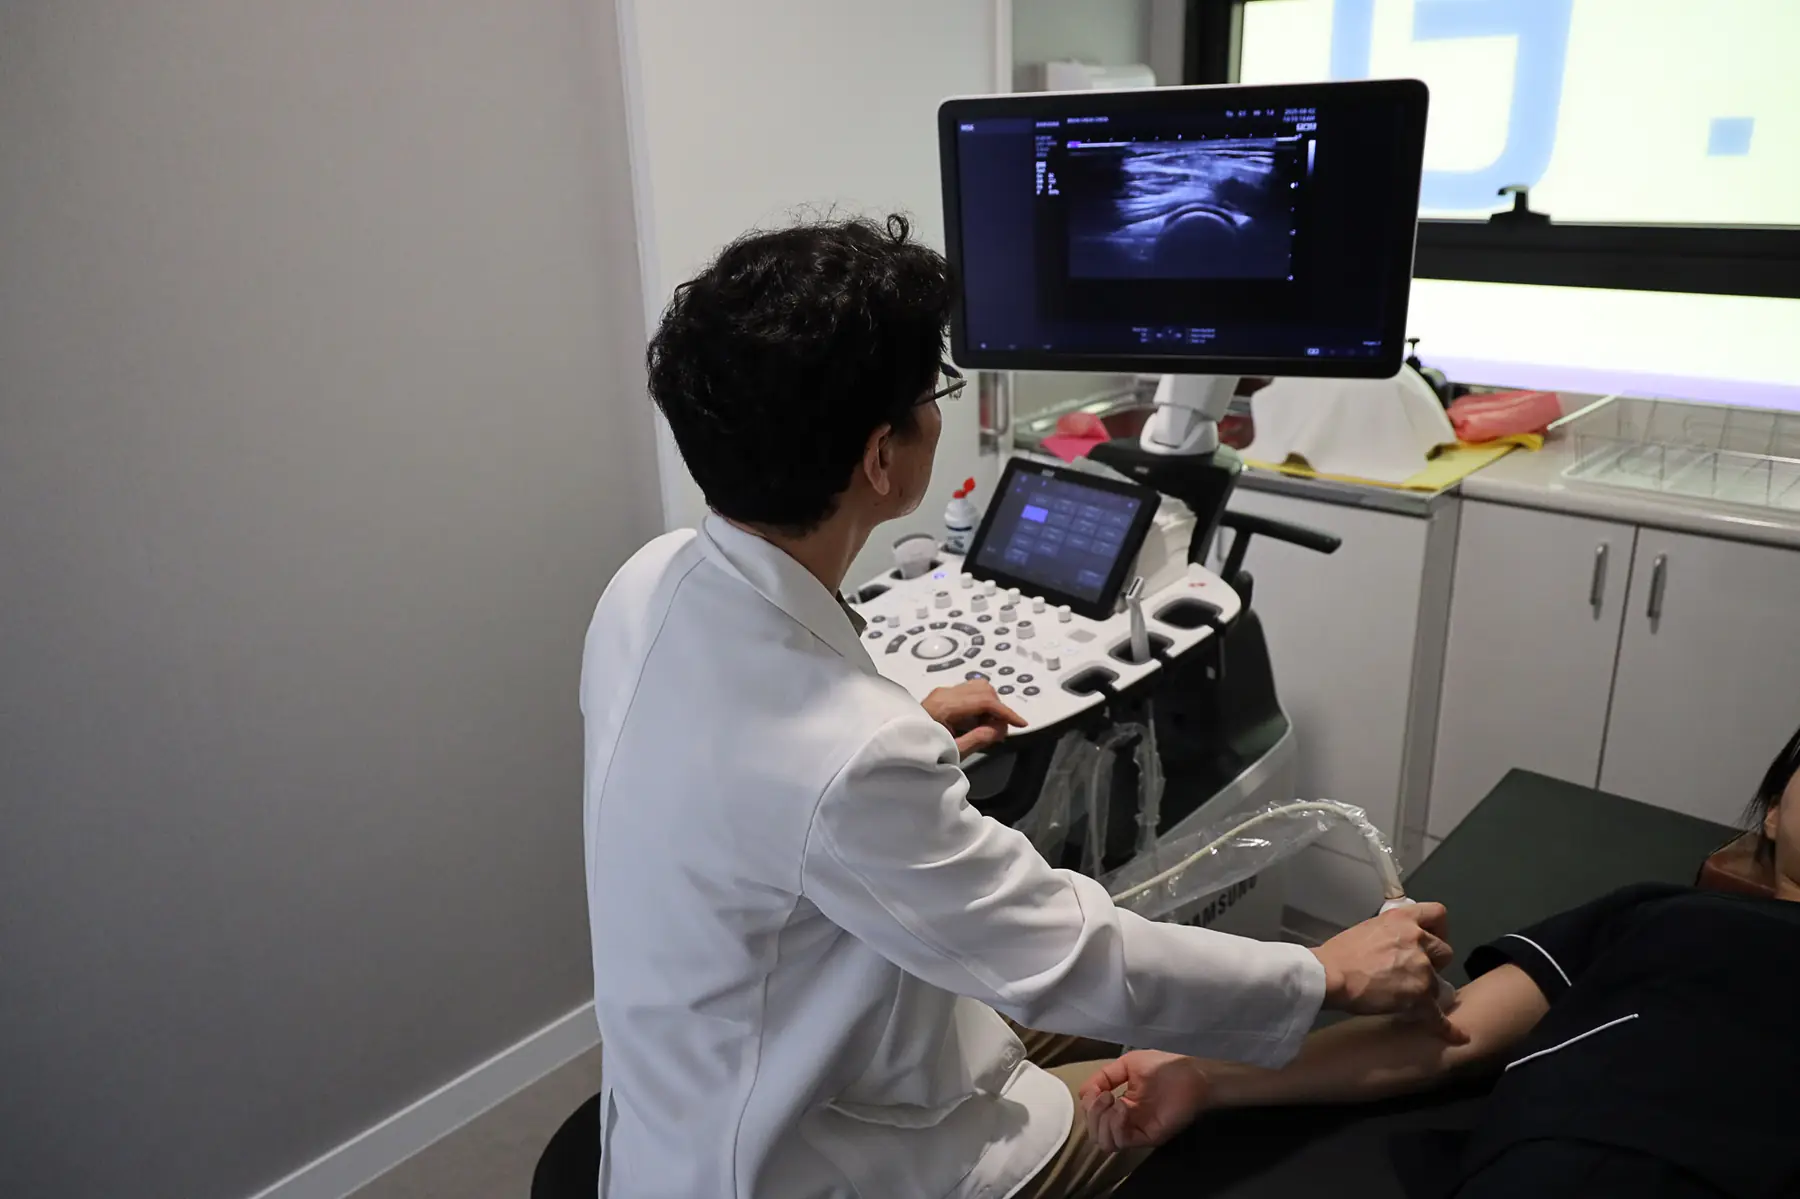

이 병원은 15년 경력의 통증 재활 전문의가 진료하며, X-ray, MRI, 초음파 등 다양한 검사를 통해 원인을 정확히 파악하고 맞춤형 치료를 제공합니다.

특히, 이상근증후군, 고관절 와순 손상, 석회성 건염 등 다양한 원인에 대해 세심한 진찰과 함께 부인과적, 내과적 문제까지 고려하는 종합적인 접근이 강점입니다.